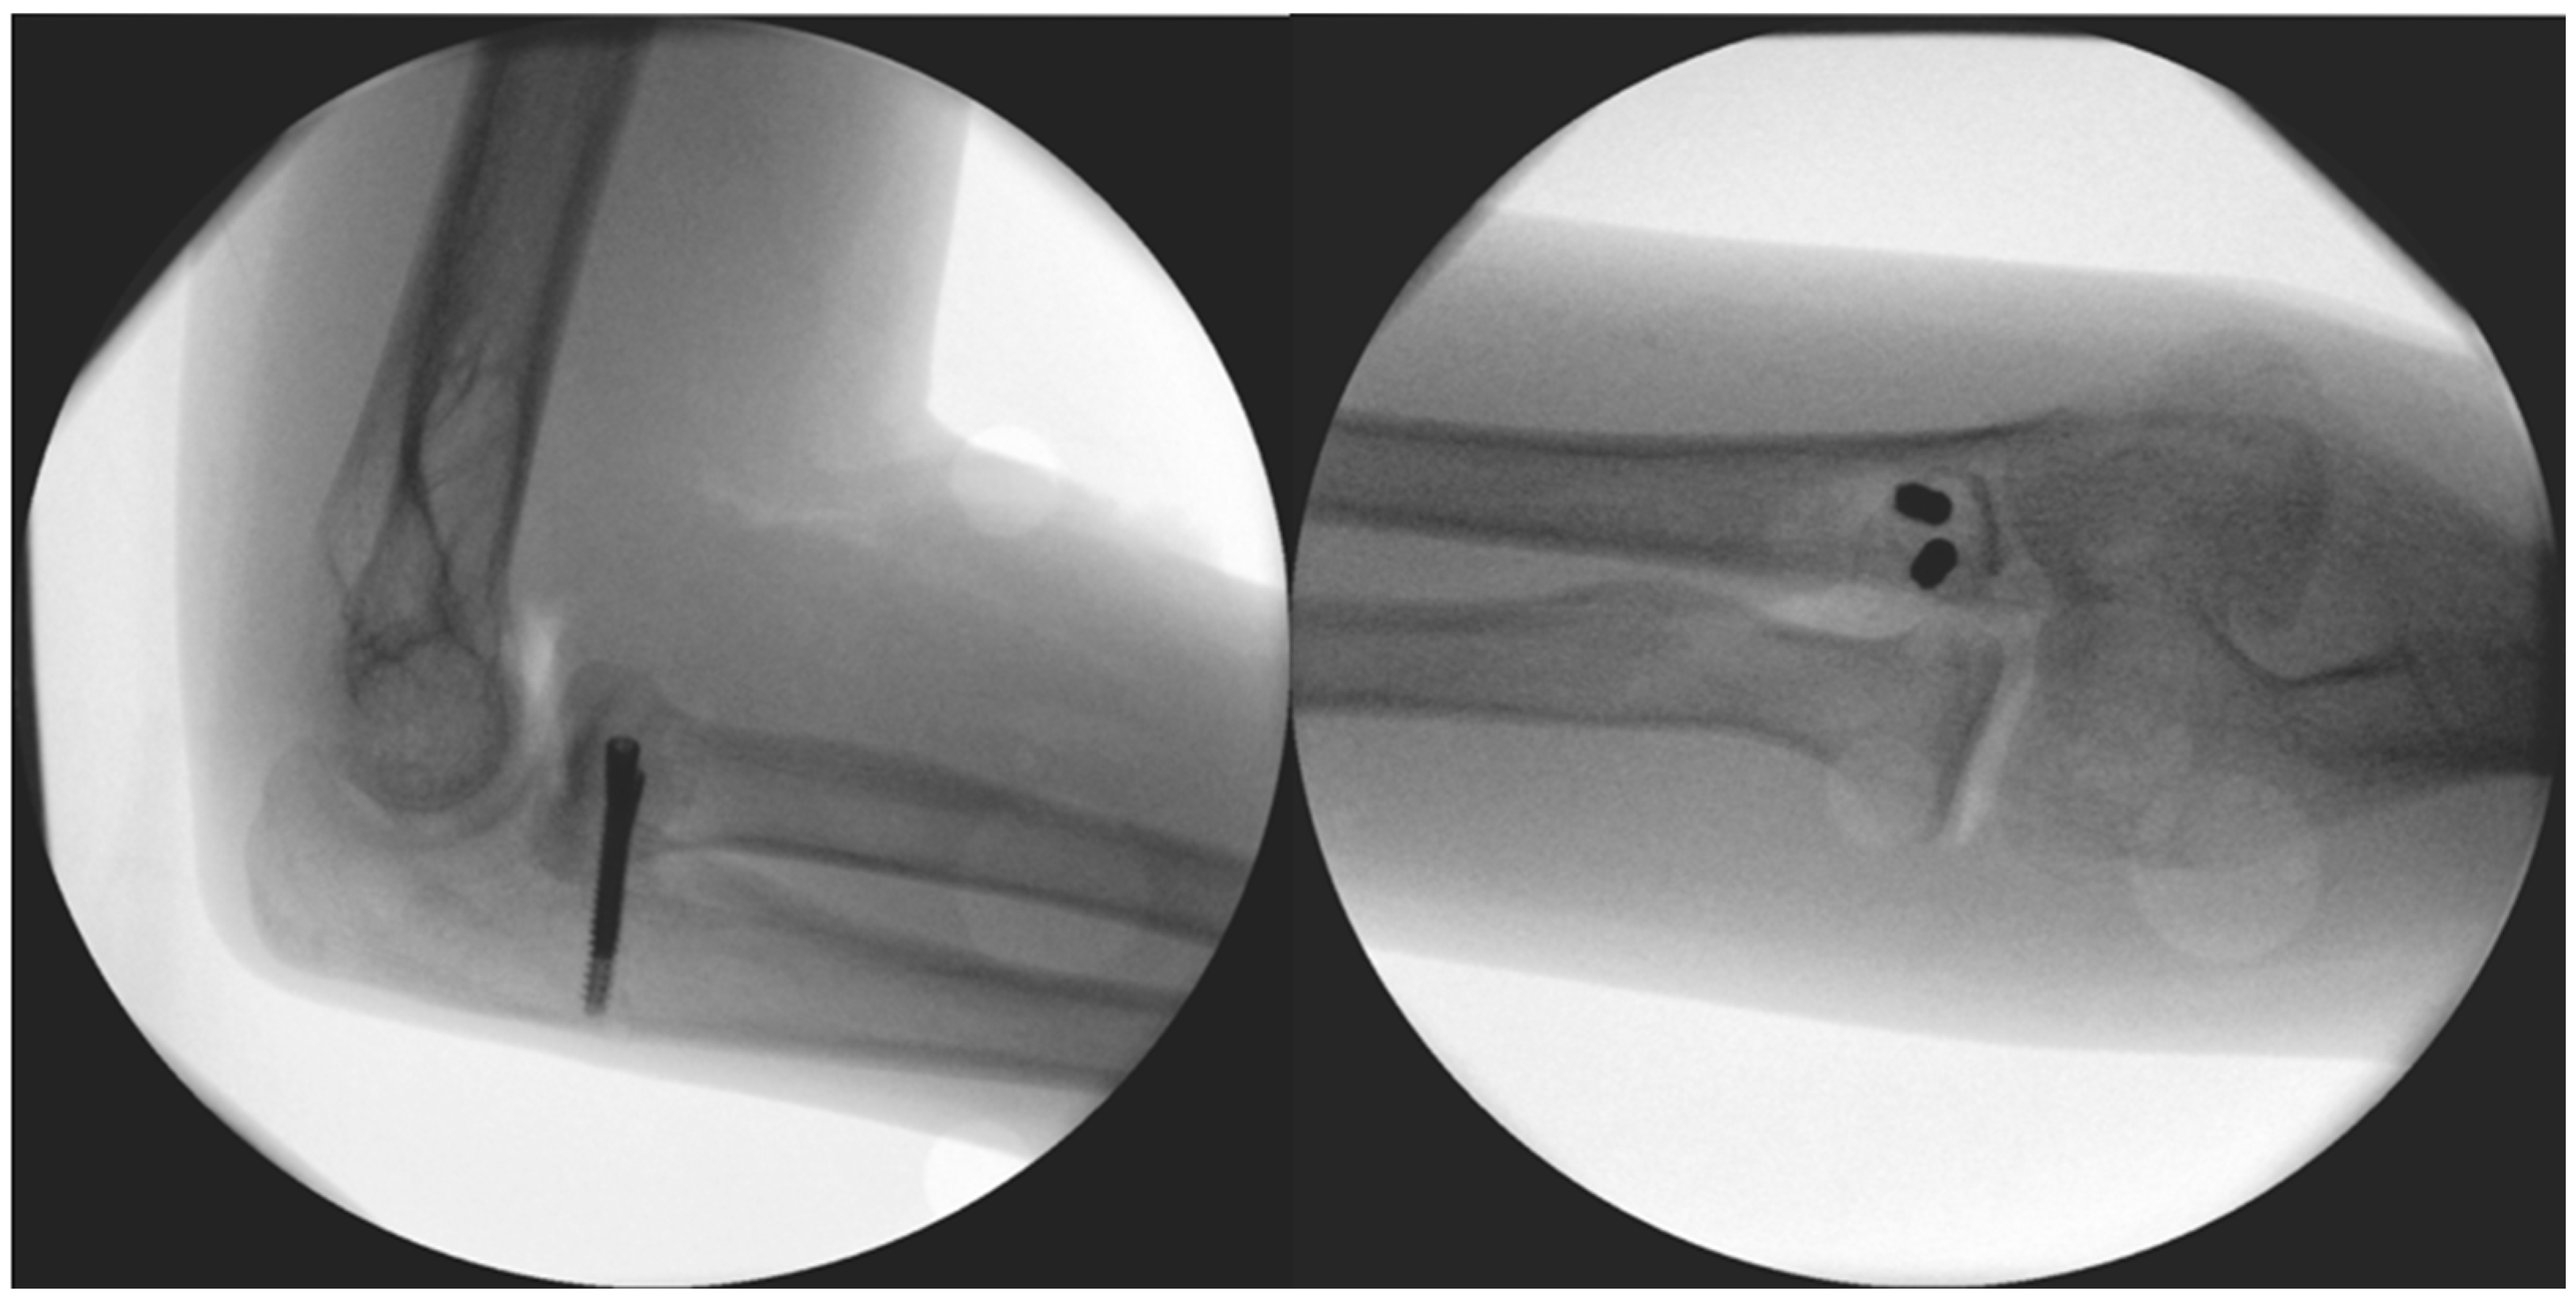

The surgery took place after disinfection and isolation, under general anesthesia, in exsanguinated conditions, and with prophylactic antibiotic protection (1 g Cefazolin) and took 90 min to complete. We used a ventral longitudinal incision along the anterior aspect of the elbow, following the modified Henry approach. After incising the skin and subcutaneous tissue, the bicipital aponeurosis was identified and carefully incised to expose the underlying brachial artery and median nerve, which were mobilized and retracted medially for protection. The biceps tendon was retracted laterally to enhance visualization. The brachialis muscle was then split longitudinally in line with its fibres, allowing access to the anterior joint capsule. Once the capsule was incised, the pronator teres was identified along its ulnar attachment and gently retracted, providing direct exposure to the coronoid process for reconstruction, facilitating precise debridement and accurate graft placement. The 2 × 1.5 × 3 millimetre (mm) bone fragment was removed. Histological analysis did not identify underlying pathology and proved that the fragment was otherwise formed of healthy bone tissue. The autograft was obtained from the iliac ala. From here, a 1 × 1 × 1 centimetre (cm) corticospongious piece was borrowed and reattached to the refreshed spongious surface of the coronoid process with two, one 26 and one 28 mm in length, A-spire (Sanatmetal Ltd., Eger, Hungary) screws (Figure 4). The graft size was determined based on the intraoperatively measured defect and used to restore anatomical height and contour to ensure joint congruity and stability. The recipient site was refreshed to gain access to a fresh vascular supply for graft incorporation with the help of a Volkmann spoon. A drain was applied, and after the reconstruction of the superficial layers, the skin was sutured. No additional reconstruction or reinforcement was needed for the median collateral ligament (MCL), as both the anterior and posterior maintained proper ligamentous integrity during the stability test. After swathing and bandaging, a 90° cast was applied, which was utilized for one month.

The surgery took place after disinfection and isolation, under general anesthesia, in exsanguinated conditions, and with prophylactic antibiotic protection (1 g Cefazolin) over 90 min. During surgery, the left elbow joint was accessed from an anterior incision, utilizing the modified Henry approach once again. The detached bone fragment was removed and replaced with a corticospongious block obtained from the iliac ala (Figure 7). Preparation of the recipient bed at the coronoid defect site was performed by removing fibrous tissue and refreshing the surface to expose healthy, bleeding cancellous bone. Subsequently, the corticospongiosal autograft was harvested from the ipsilateral iliac ala. The graft was carefully shaped intraoperatively to match the defect dimensions accurately, ensuring an optimal fit to restore the anatomical contour of the coronoid process. This technique aimed to facilitate biological integration and promote rapid healing. The graft was fixed in its final position with two Herbert screws (Johnson & Johnson: Depuy Synthes, Oberdorf, Switzerland). A drain was applied, and after the repair of the subcutaneous layers, the skin was sutured. Following swathing and bandaging, the left upper extremity was immobilized with a long upper limb cast.

Figure 4. Immediate post-op images of the fixation.